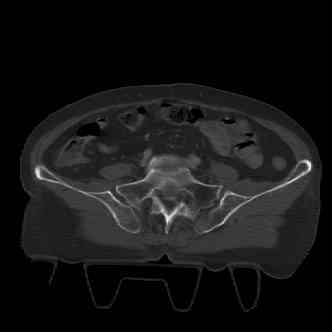

attached are several CT cuts. please let me know if you need more. the CT is pre-pelvic ex-fix placement.

I wouldn't plate the front.

But I would add screws posteriorly.